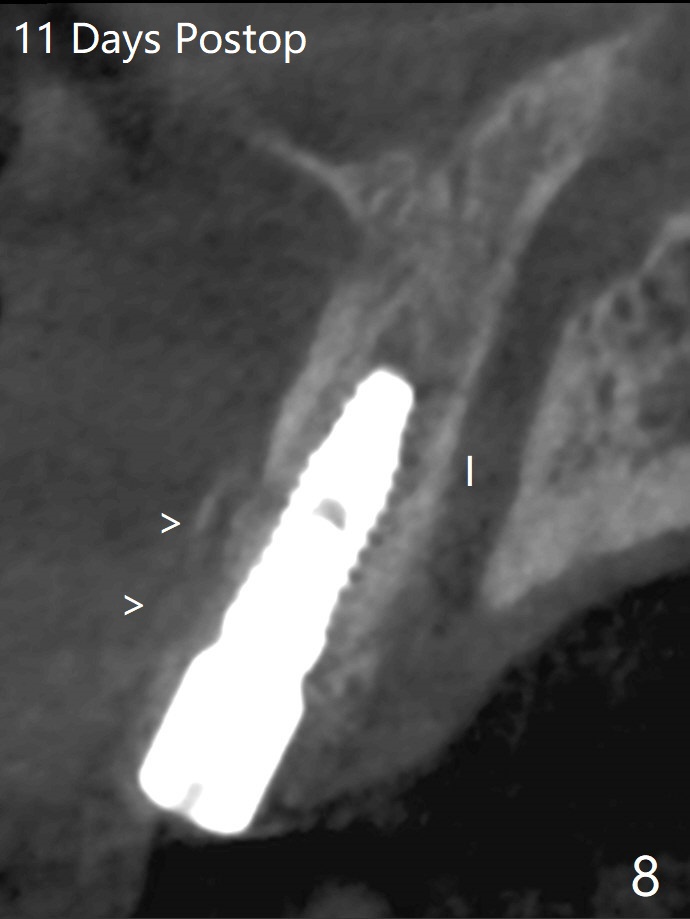

左上1(图一)拔除,植骨,使用带钛架不可吸收膜(图二)后十个月准备植牙(图三),在没有术中根尖片指导下(导板习惯),在牙槽嵴正中开始钻洞,第一个钻头最后一两个毫米觉得有突破感,但是颊侧舌侧没有穿孔,然后植入3.5x11.5毫米植体(图五,扭力>35 Ncm),术后射线表明植体接近切牙管(图四:*)。考虑到病人要离城,颊侧第一螺纹暴露(图六),舌侧骨板薄(图五),植骨,放置愈合基台(图七)。 术后十一天CT显示植体没有侵犯切牙管(图八:I);植体颊侧骨粉(箭头)似乎可以解释颊侧饱满(图九)。第二原因是减张缝合,胶原膜暴露(*),而下面骨粉没有暴露,以后伤口应该是二期愈合。